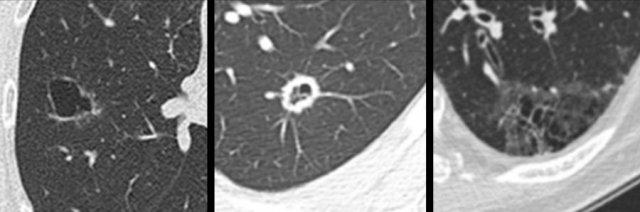

Ví dụ minh họa sự chuyển đổi từ hình thái kính mờ thuần túy (bảng trái) sang hình thái ung thư phổi dạng nang (bảng phải).

Ví dụ minh họa sự chuyển đổi từ hình thái dạng nang (bảng trái và giữa) sang hình thái ung thư phổi bán đặc (bảng phải).

Ví dụ này minh họa sự chuyển đổi từ hình thái bán đặc (bảng trái), sang hình thái dạng nang tạm thời (bảng giữa), rồi đến hình thái ung thư phổi đặc (bảng phải).